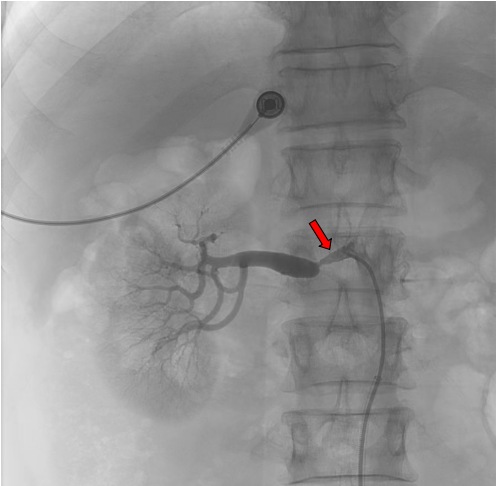

微信图片_20240411093454.png

血管CTA图像(红色标记为右肾动脉狭窄部位)